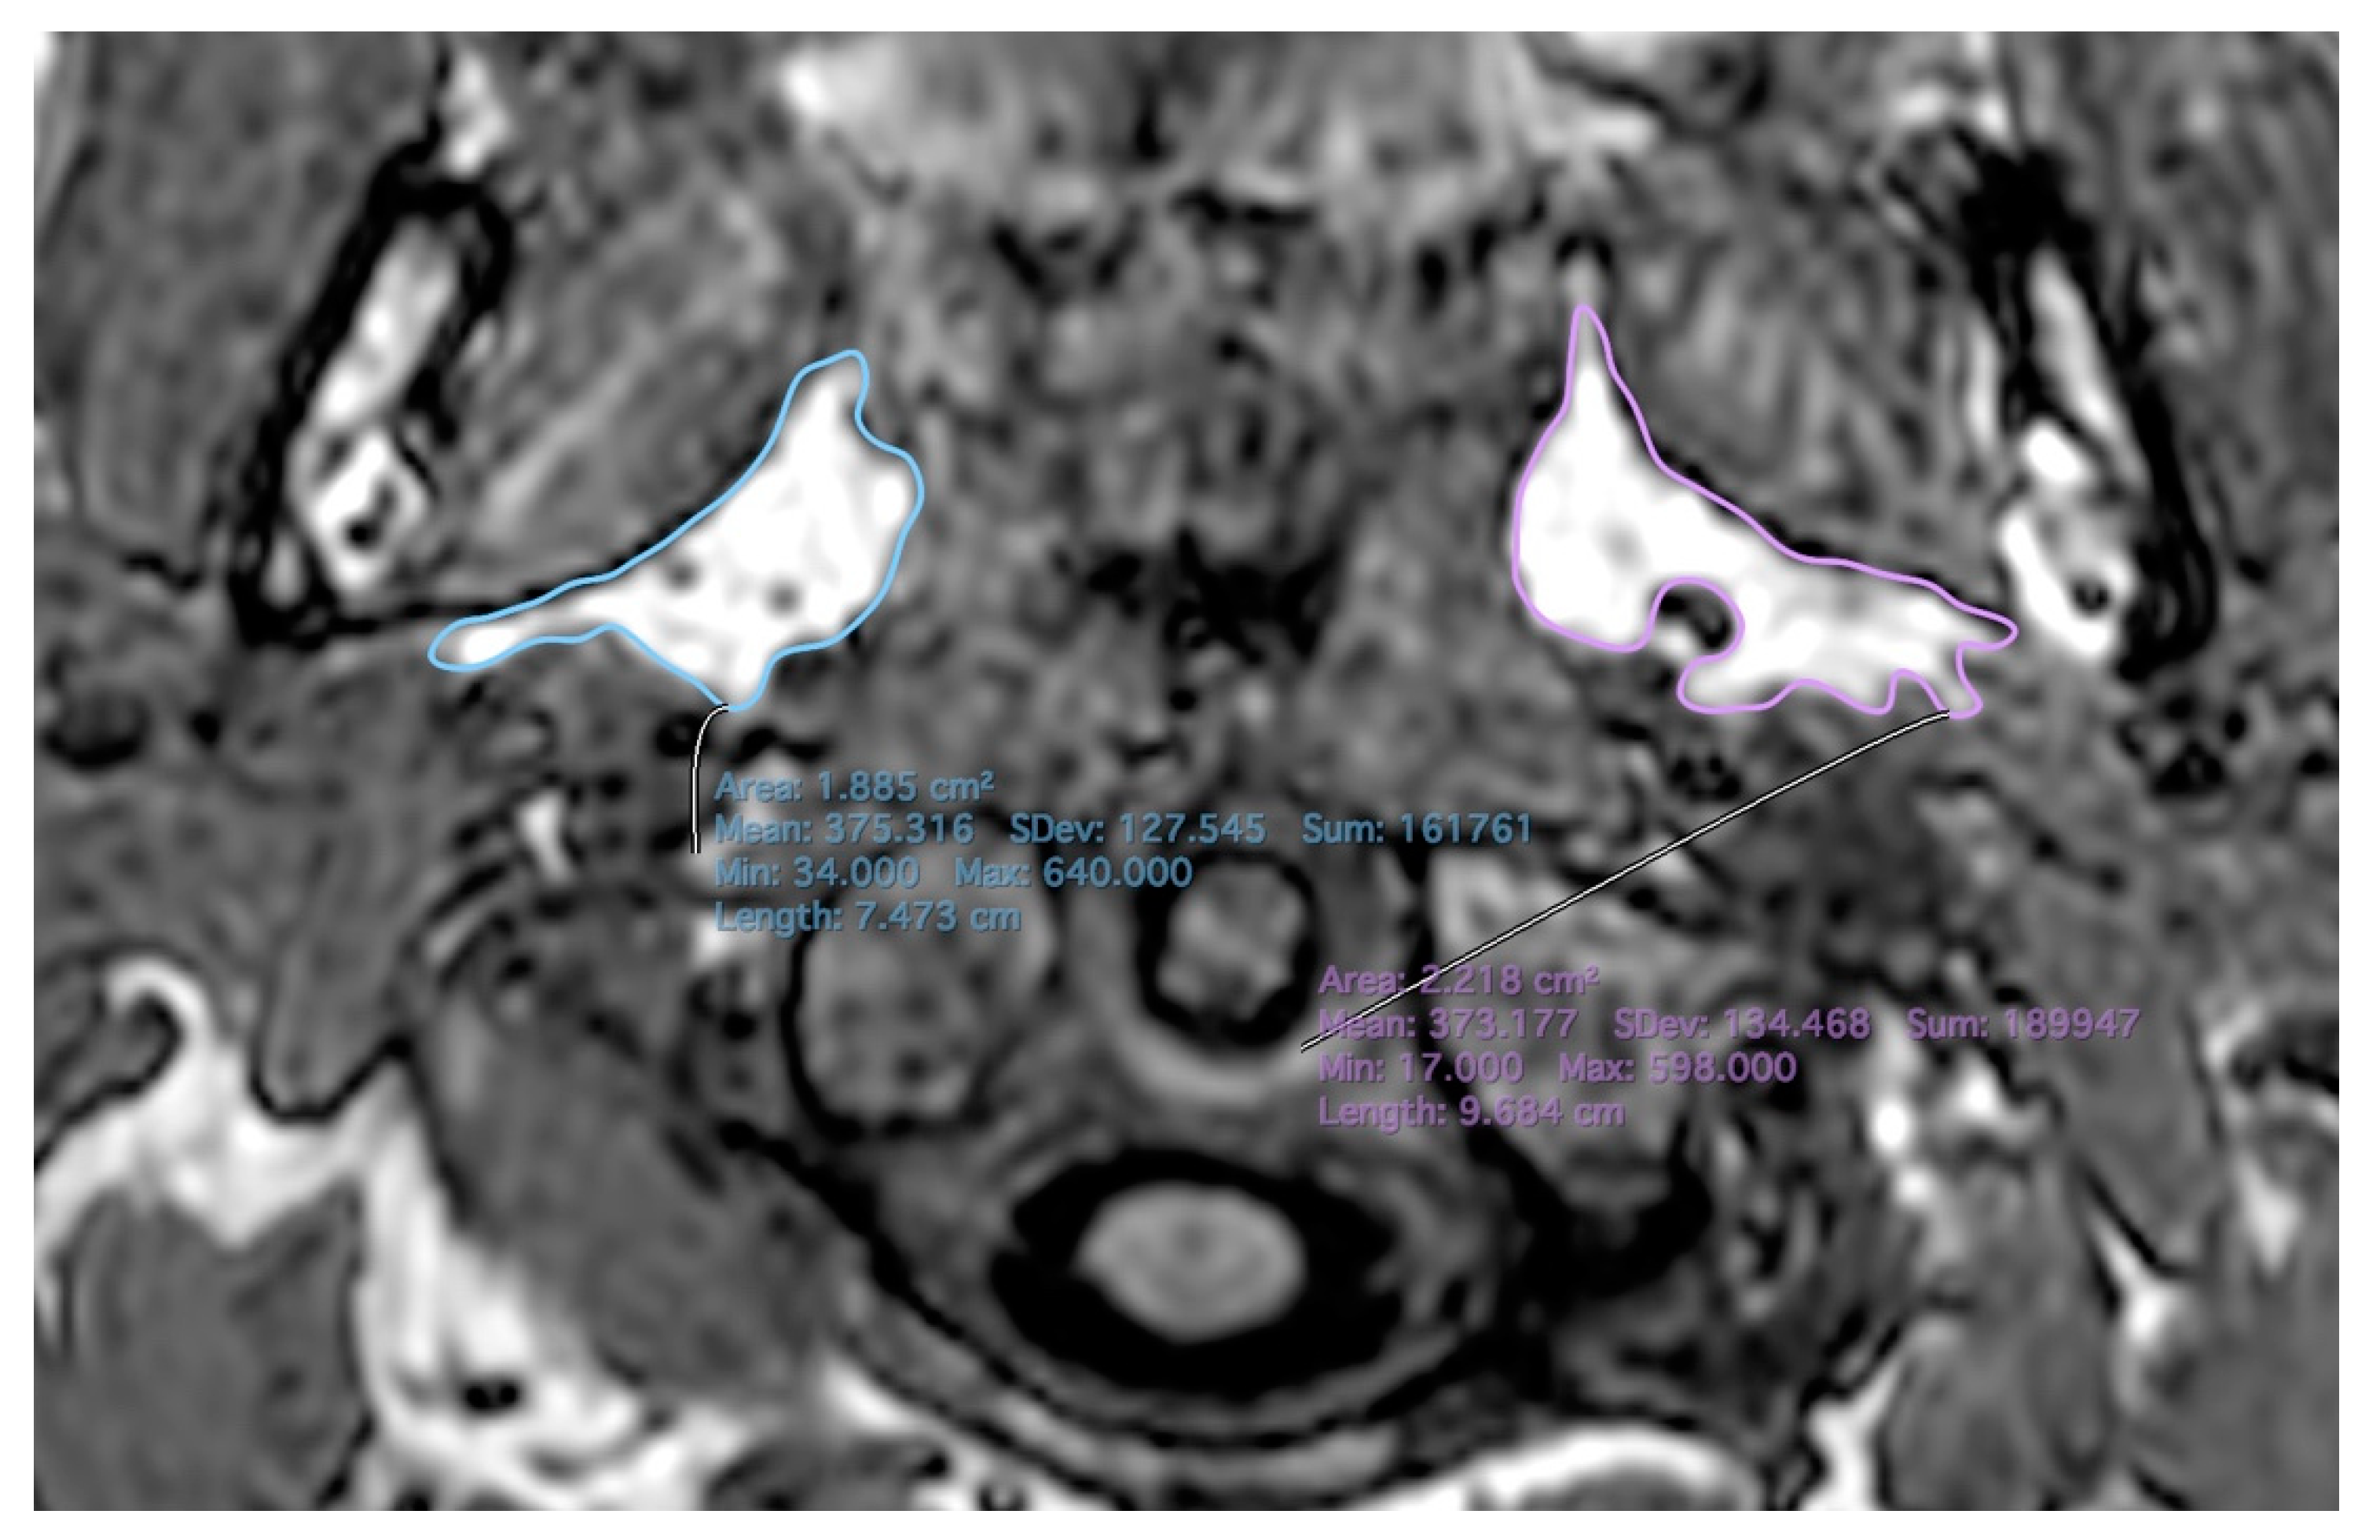

| Parapharyngeal fat area (right) | A: 0 | C: 0.582 (0.328, 0.756) | E: 0.418 (0.244, 0.672) |

| Parapharyngeal fat area (left) | A: 0 | C: 0.631 (0.388, 0.789) | E: 0.369 (0.211, 0.612) |

| Pharyngeal wall-parapharyngeal fat (right) | A: 0 | C: 0.549 (0.281, 0.735) | E: 0.451 (0.265, 0.719) |

| Pharyngeal wall-parapharyngeal fat (left) | A: 0 | C: 0.52 (0.247, 0.714) | E: 0.48 (0.286, 0.753) |

| Pharyngeal wall-internal carotid artery (right) | A: 0 | C: 0.511 (0.234, 0.709) | E: 0.489 (0.291, 0.766) |

| Pharyngeal wall-internal carotid artery (left) | A: 0 | C: 0.484 (0.206, 0.689) | E: 0.516 (0.311, 0.794) |